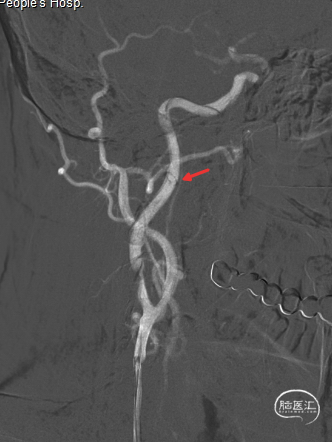

扩张完毕后多角度造影显示狭窄较前明显改善(箭头处)。